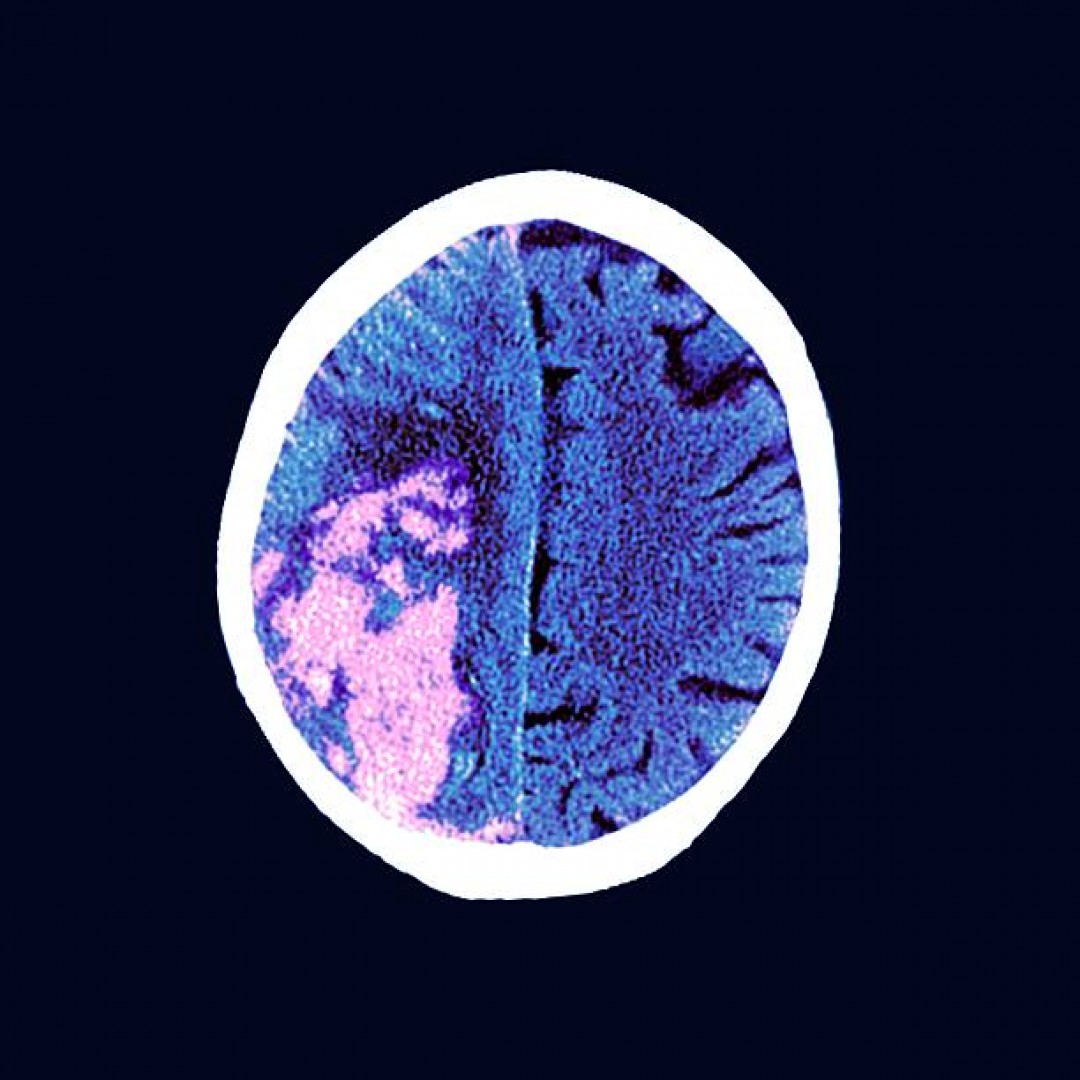

Enfermedad CerebroVascular